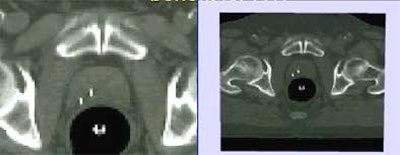

![]() |

| Anatomic MRI with CT (left) and functional MRI with CT (right) show tumors and markers. |